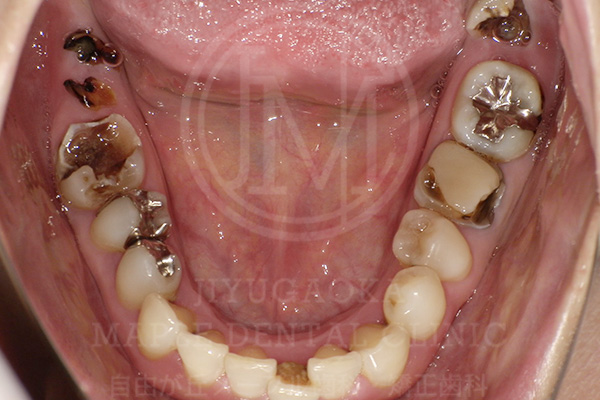

前述した通り、銀歯治療は構造的・素材的な特性から、虫歯の再発(=二次虫歯)リスクが高くなる傾向があります。ここでは当院にご来院された方の銀歯の下で虫歯が広がってしまっていたケースを紹介します。

銀歯の下で虫歯が

広がってしまっていた症例

銀歯を外す前

銀歯を外した後